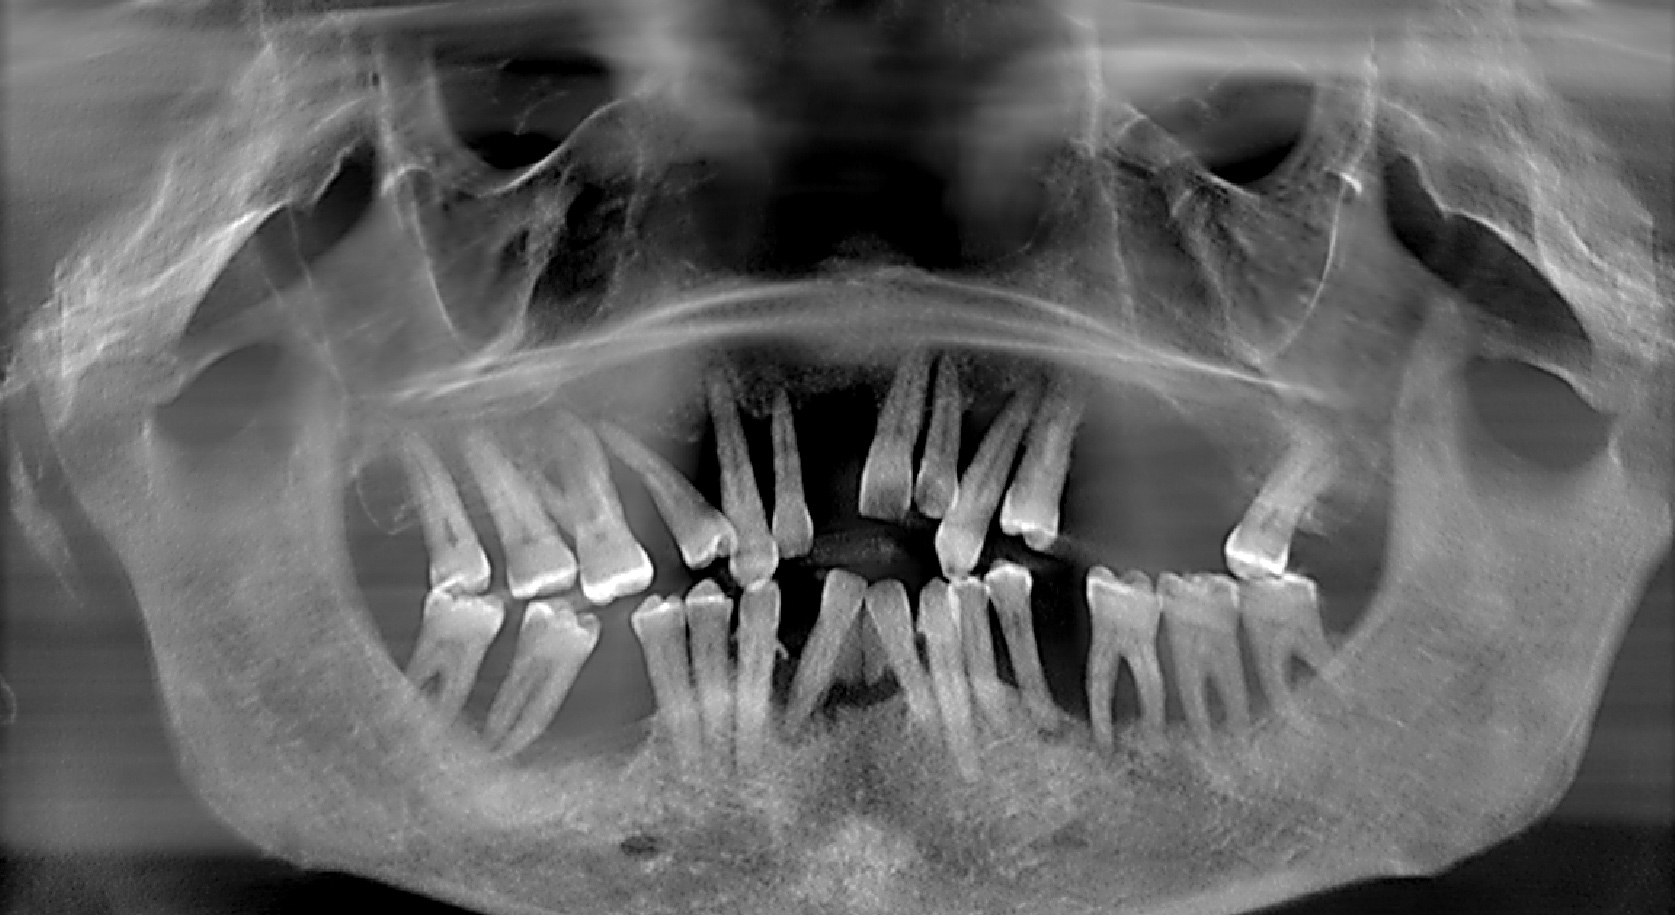

Fig 1. Presurgical panoramic radiograph of a patient with severe periodontal disease and who is an All-on-4–style treatment candidate.

Figure 1